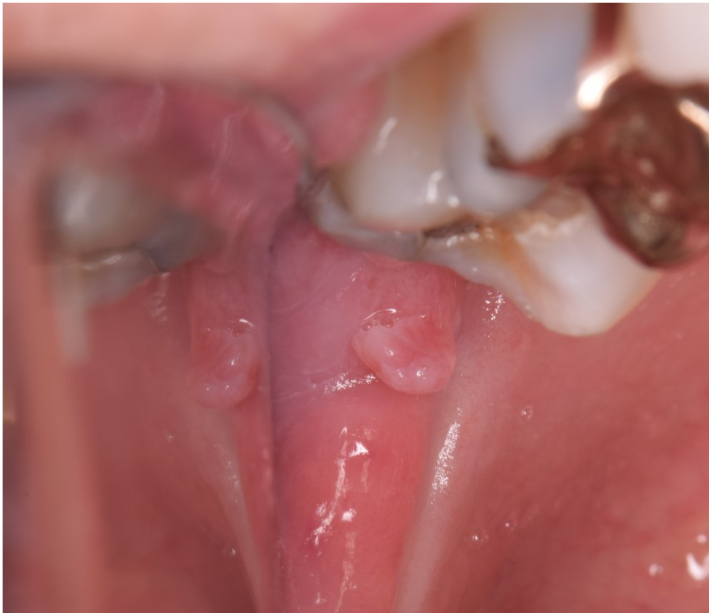

Answer: B. Squamous papilloma

This month’s case features a squamous papilloma. These are very common benign lesions, occurring in 1 of 250 patients. Squamous papilloma’s are the most common epithelial tumor of the soft palate. They have a low virulence and infectivity rate, meaning they are not very contagious. Lesions tend to present as pedunculated, exophytic, white or mucosal-colored, wart-like growths and are typically about 0.5 cm in greatest diameter. These lesions are not considered sexually transmitted, nor do they have any association with HPV-driven oropharyngeal squamous cell carcinoma. Treatment is conservative surgical excision with an excellent prognosis.